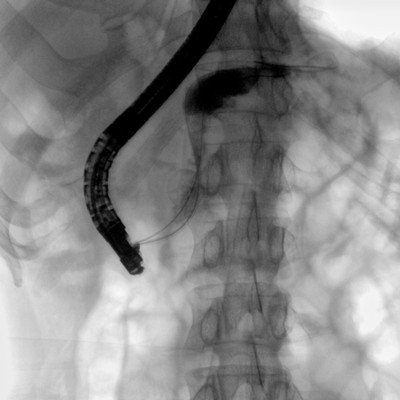

可用于常規(guī)的外周血管介入手術,設備的移動性好,對手術室空間要求低,可滿足長時間X光透視的需求,且增加了獨特的血管影像處理功能,是開展介入手術的理想設備。

優(yōu)質平板探測器、可靈活升降調節(jié)SID、獨特圖像處理系統(tǒng)、高品質濾線柵,大視野成像清晰不失真。

采用智能劑量控制技術,可根據(jù)不同體型和不同部位,準確調節(jié)投照劑量。使操作者在任何使用環(huán)境下,都能實現(xiàn)低劑量、診視圖像清晰的效果。

采用電動機架設計,可以實現(xiàn)C形臂繞水平軸旋轉、沿弧滑動、上下升降、 水平延伸四方向電動運動,充分滿足臨床擺位需求。